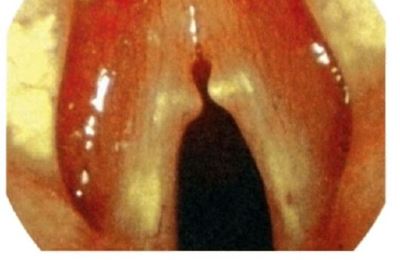

Пациент 11 лет, был направлен на прием к лору с жалобами на затрудненное дыхание, сухость в горле и осиплость голоса. При осмотре: общее состояние ребенка не нарушено, слизистая гортани гиперемирована, отечна, голосовые складки розовые, смыкаются не полностью. Диагноз: катаральный острый ларингит.

Назначено лечение: голосовой покой, диета, гортанные заливки с масляным раствором витамина Е, щелочные ингаляции и Эфизол (пастилки для рассасывания).

Через неделю состояние ребенка нормализовалось и он вернулся к привычному образу жизни.